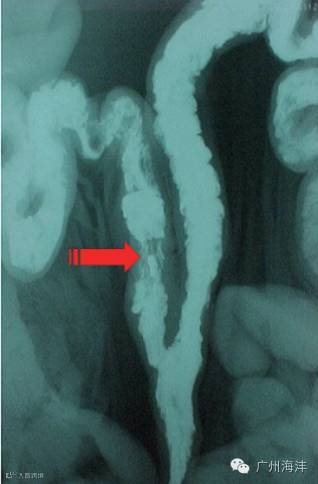

PCAI:子宫颈后人工授精, 与常规子宫颈内授精相比, 在将常规输精管插入子宫颈皱褶后, 再插入一个细的、半软的输精内管, 它比常规输精管长16cm, 可以通过子宫颈皱褶进入子宫体。

子宫体输精精液的分布情况